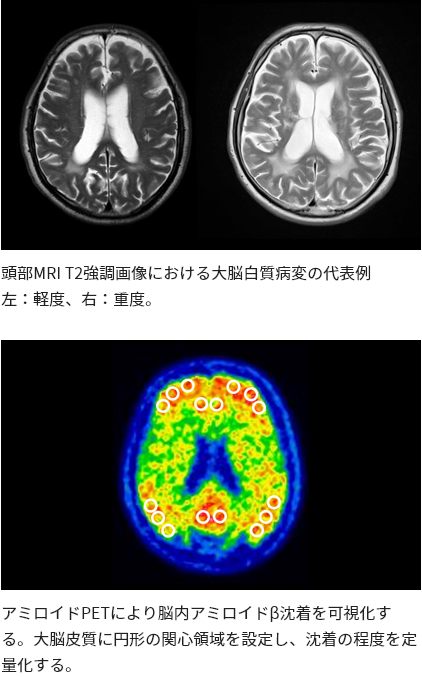

私たちのグループでは、アルツハイマー病における脳の虚血性変化や大脳白質病変(White matter lesions:WML)が認知機能に与える影響を研究してきました。これまでの研究では、脳虚血変化が強い患者さんでは、脳アミロイドβ蓄積が比較的軽度であっても認知機能低下を来しうること、またWMLの重症度が認知機能低下と関連することを明らかにしてきました。アルツハイマー病ではアミロイドβの蓄積だけでなく、脳の虚血性変化や微小血管障害も認知機能に関与することが示されており、血管危険因子の適切な管理が認知症予防につながる可能性があります。現在進めているMCI・軽症認知症の研究も、こうしたこれまでの知見を基盤として発展させたものです。